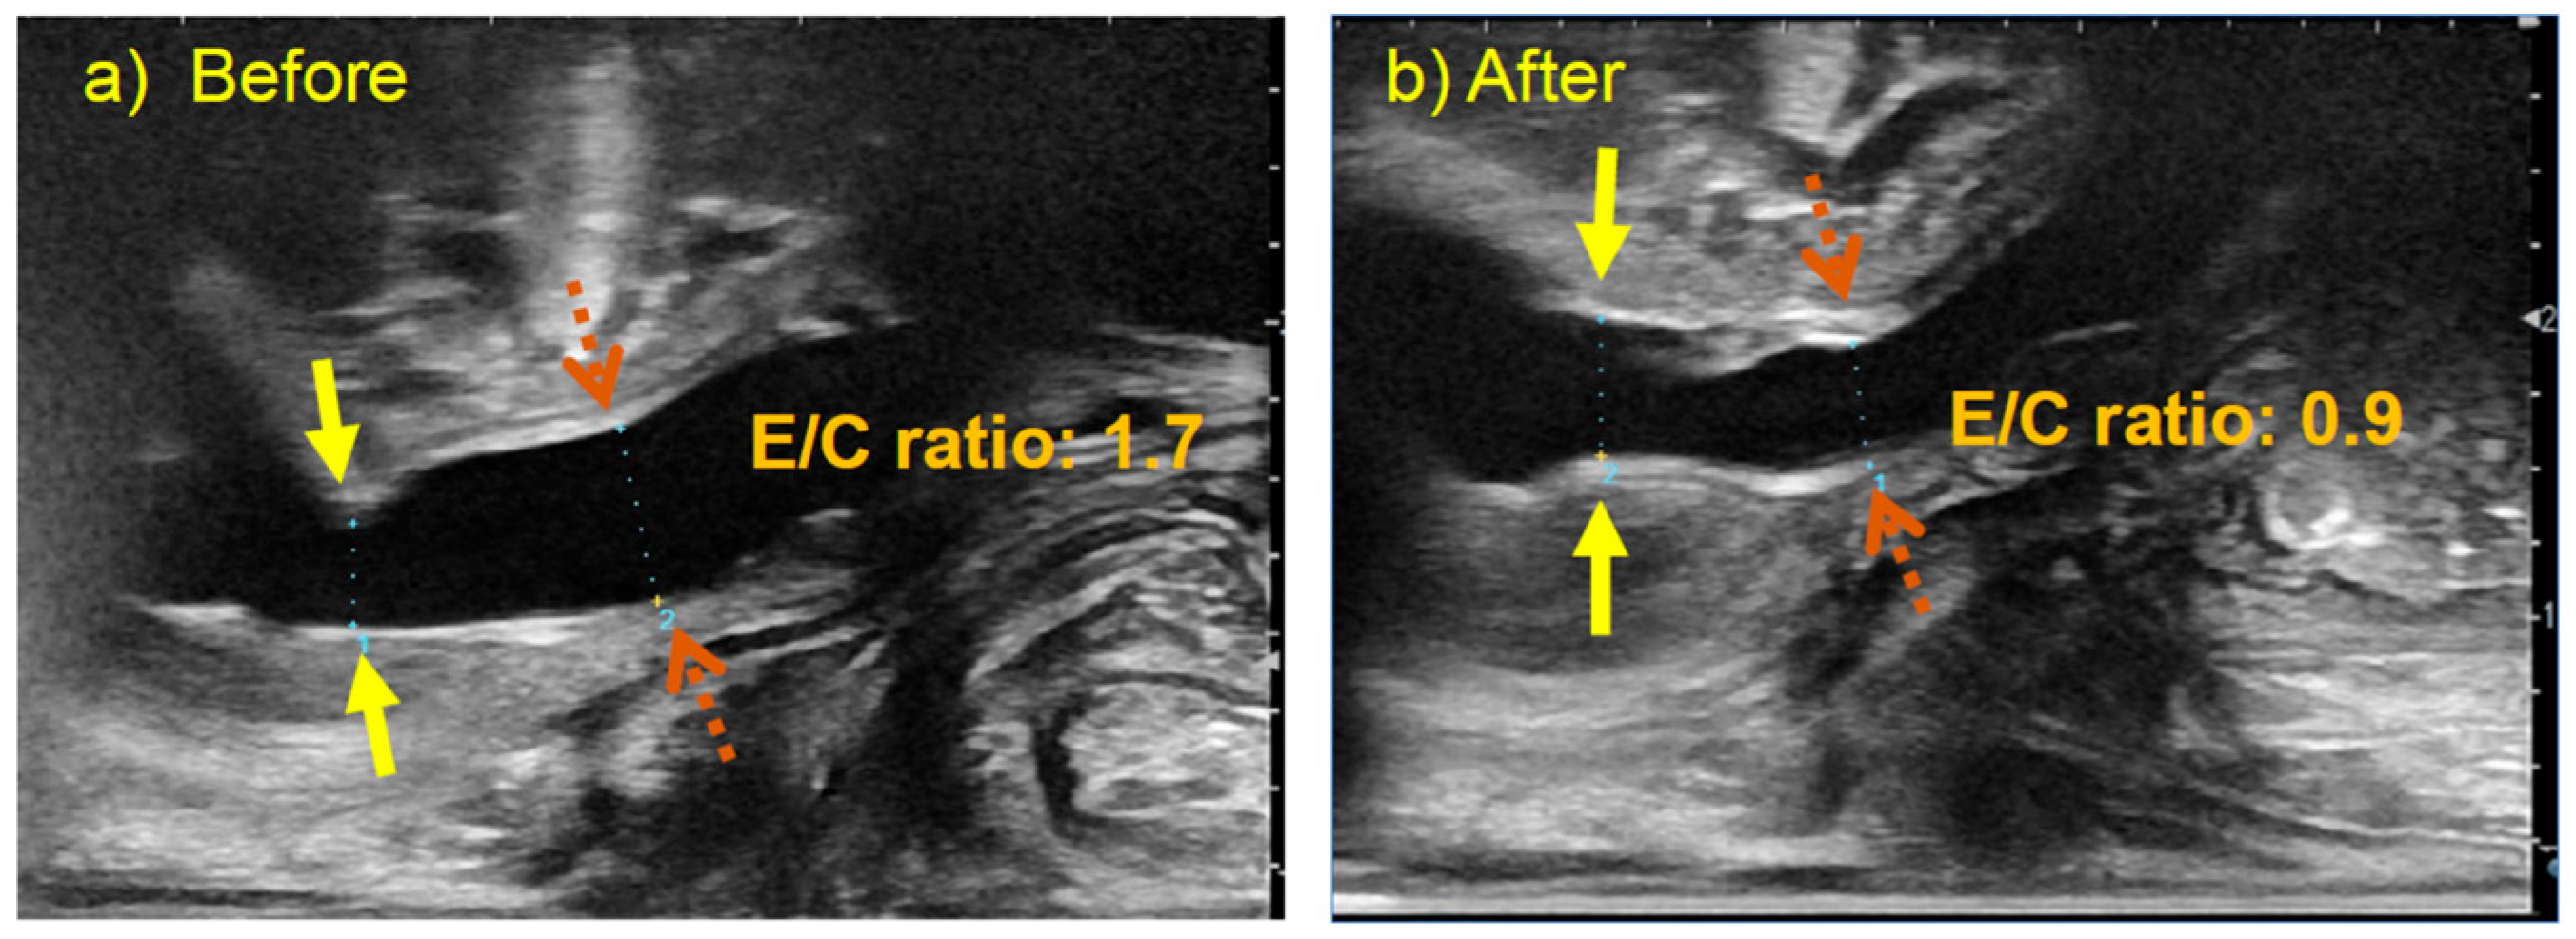

Figure 2. Comparison of urethral ultrasound images before and after urethral incision in a 2-year-old with PUV. Yellow solid arrows indicate the constricted (C) portion, and brown dashed arrows indicate the expanded (E) portion of the urethra. (a) Ultrasound finding before the urethral incision. The posterior urethra is dilated because of PUV. Urethral diameter at the (C) and (E) were 3.3 mm, 5.7 mm, E/C ratio: 1.7. (b) Ultrasound finding after the urethral incision. The narrow portion of the urethra due to PUV is relieved. Urethral diameter at the (C) and (E) were 4.7 mm, 4.1 mm, E/C ratio: 0.9. PUV: posterior urethral valves, E/C ratio: ratio of the diameters of the constricted (C) and expanded (E) portions of the urethra.

Furthermore, the diameters of the C and E segments of the urethra before and after RUG-TUI were compared. The median preoperative diameters of the E and C segments of the urethra were 5.0 mm (range, 3.3–8.0 mm) and 3.1 mm (range, 1.6–5.7 mm), respectively, with a median E/C ratio of 1.7 (range, 1.2–2.7). The median postoperative diameters of the E and C segments of the urethra were 5.0 mm (range, 3.1–6.6 mm) and 5.5 mm (range, 4.1–8.0 mm), respectively, with a median E/C ratio of 0.9 (range, 0.7–1.2). The diameter of the C segments and the E/C ratio revealed a significant difference between the preoperative and postoperative measurements (p < 0.0001) (Figure 3).